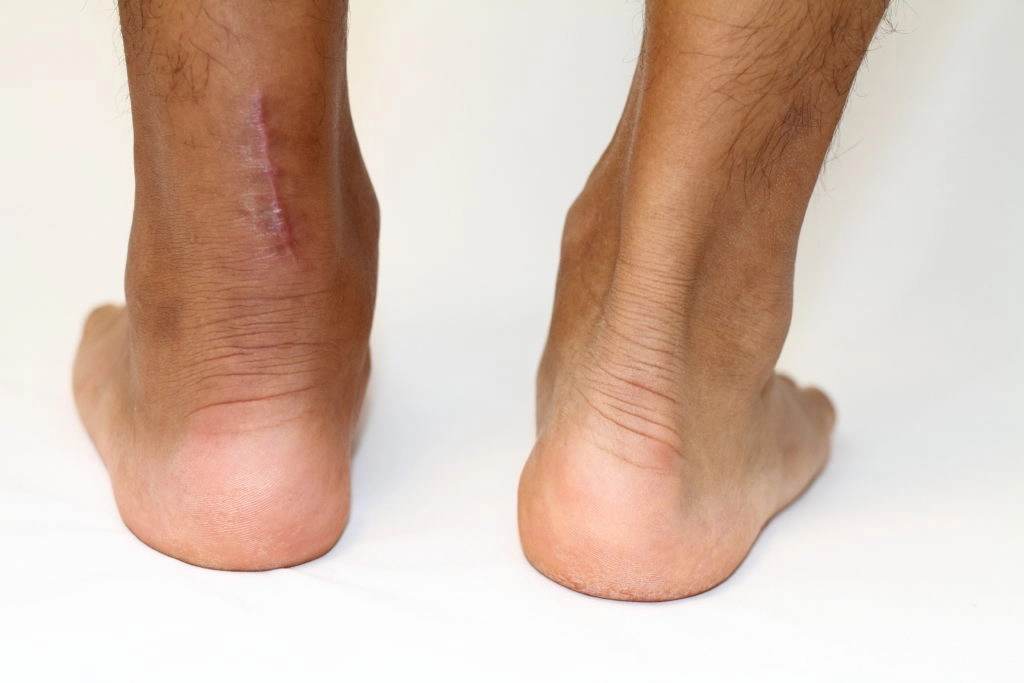

12ヶ月後の状態に差はありません。瘢痕(傷跡)がないので可動域を確保し、最短でスポーツ復帰

手術では必ず皮膚を切ります。

切った部分は手術跡(瘢痕:はんこん)となり、皮膚が硬くなり可動域を制限します。

瘢痕は皮膚表面だけではなく、内部のアキレス腱周囲にも生じます。だから、傷口を作らない保存療法がオススメなのです

傷口は繊維組織というもので接着剤のようにして傷口を塞ぎ、

その際に皮膚や皮下の組織がくっつき合ってしまいます。つまり、手術跡は可動域を制限する大きな原因となります。

一方、保存療法で手術跡は残りません。

手術跡がない分、可動域は出やすいです。スポーツ復帰には保存療法で「傷跡なし」が大切。